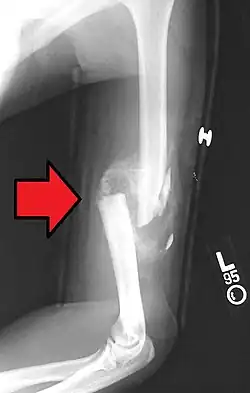

A spiral fracture of the distal one-third of the humerus shaft -